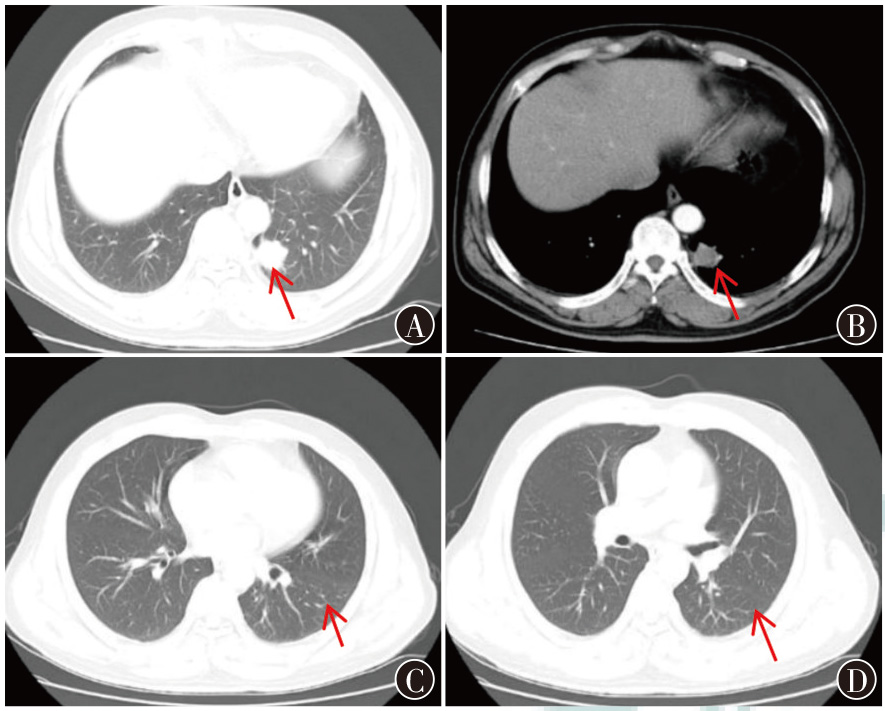

表皮生长因子受体(EGFR)基因L858R突变和棘皮动物微管相关蛋白样4-间变淋巴瘤激酶(ALK)基因融合肺腺癌是一种具有特定分子特征的恶性肿瘤,其恶性程度较高,且对传统治疗手段反应有限。分子靶向治疗是一种精准治疗策略,它通过特定的分子药物针对肿瘤细胞的特定分子靶点发挥作用,从而抑制肿瘤的生长和扩散。现报道1例EGFR基因突变和ALK基因融合肺腺癌的诊疗过程,复习相关文献并讨论,以期为临床提供诊疗思路。